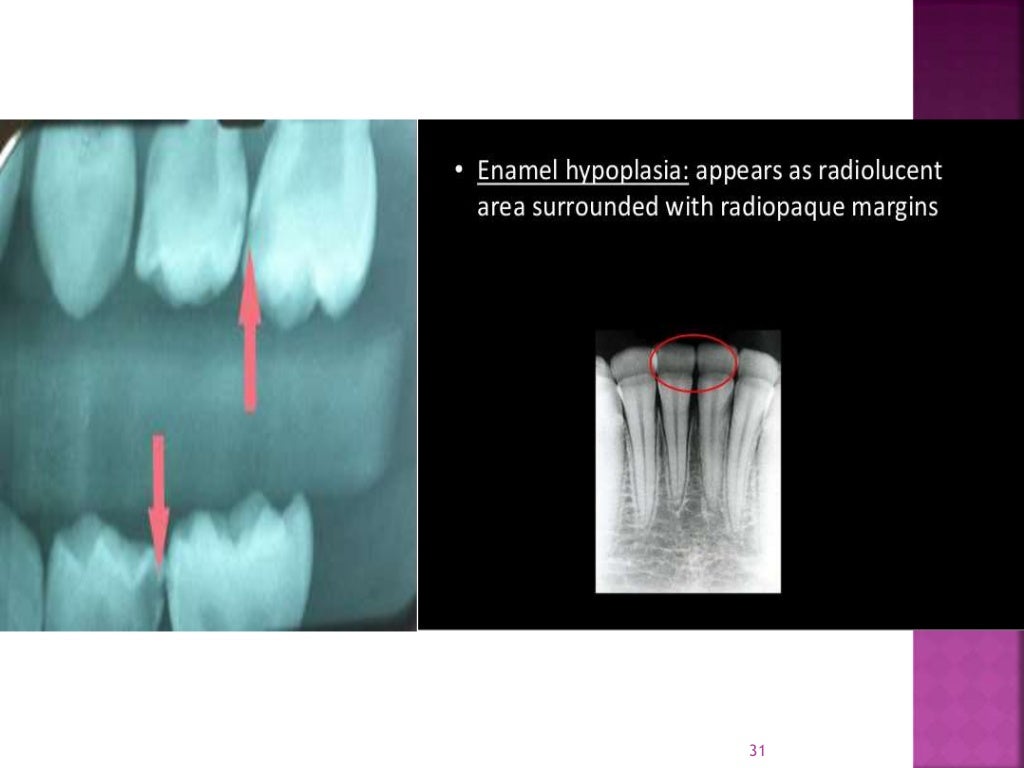

Enamel hypoplasia ppt What Does Enamel Hypoplasia Mean Quizlet This occurs to primary and/or succedaneous teeth. Enamel hypoplasia is when your tooth enamel doesn’t develop properly, causing it to be too thin or missing on parts of. Still, it can affect both baby teeth and permanent teeth. Enamel hypoplasia is a defect of the enamel that only occurs while teeth are still developing. Reduced enamel formation during embryonic development. What Does Enamel Hypoplasia Mean Quizlet.